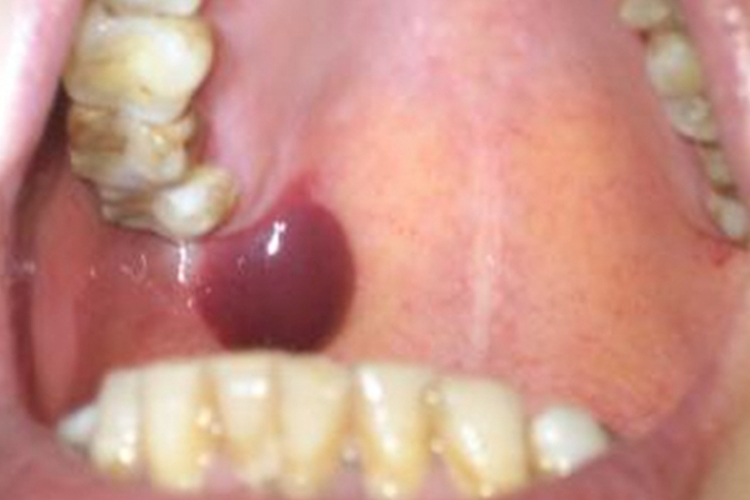

创伤性血疱引起的血疱往往较大,可达20-30mm,近咽喉处的大血疱可引起反射性恶心。初起疱液鲜红,看起来像血包,旋即变为紫黑色,疱壁薄容易破裂,瘀血流尽后留有鲜红色疱底创面,疼痛明显,影响吞咽。一般愈合较快,有继发感染则形成糜烂或溃疡。

良性黏膜类天疱疮会反复出现疱壁较厚的张力性水疱或血疱,看起来像个血包,不易溃破,破溃后形成糜烂,累及牙龈会呈现龈缘弥漫性红斑,愈合后会形成白色纤维网状瘢痕。